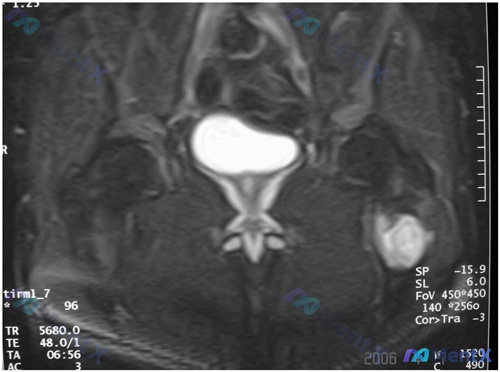

整理到一份腰椎影像学病例资料,先放核心信息出来: 基础影像表现: - 腰椎椎体(L4)可见明显溶骨性骨质破坏,左侧椎体后缘及侧缘骨皮质连续性中断 - 椎体内部骨小梁结构紊乱,病灶边缘模糊,未见明确骨膜新生骨 - 椎体形态改变,左侧轮廓向外膨出,后缘向椎管内突入,疑似软组织肿块影占据椎管左侧区域 -...

整理了一个很有特征性的骨盆肿瘤病例,从主诉到影像再到分析思路都走一遍,欢迎讨论~ --- 病例基本信息 - 患者:56岁男性 - 主诉:慢性、进行性加重的下背痛数月,伴左腿放射痛,夜间加剧 - 既往史:无特殊,未常规服药 - 生命体征:体温正常,血压、脉搏、呼吸频率均平稳 查体与初步影像 - 触诊左...